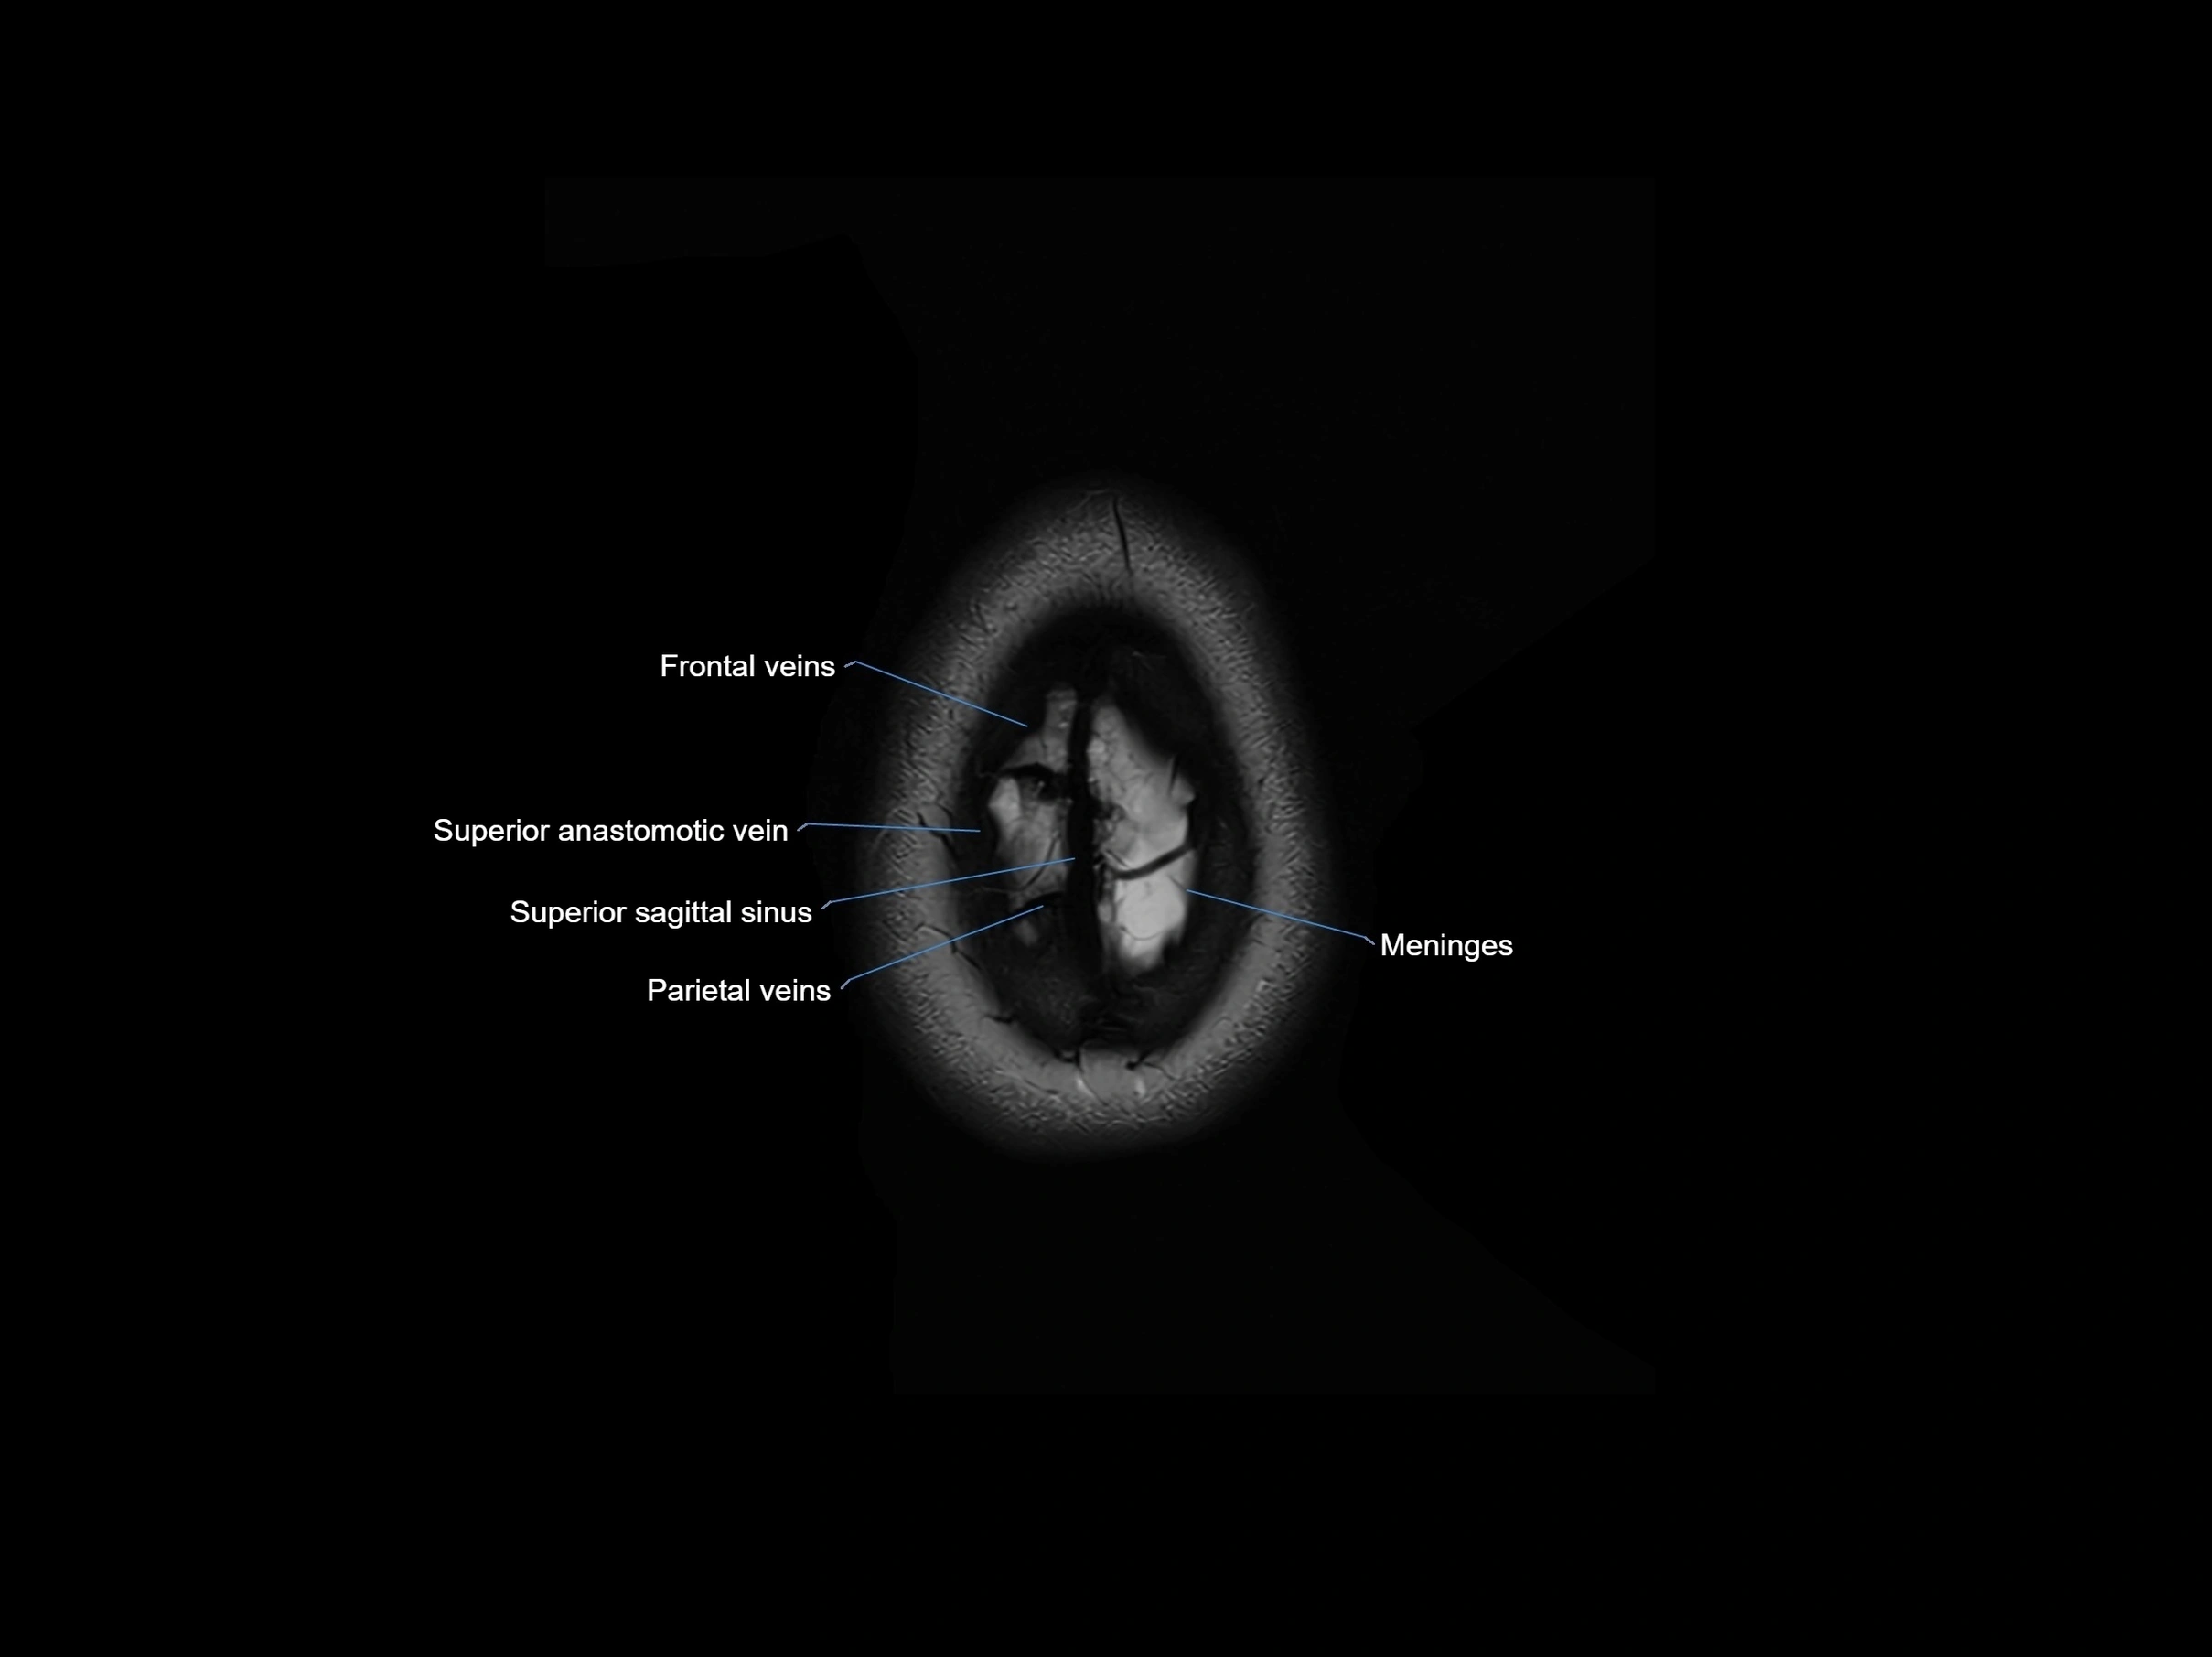

MRI images